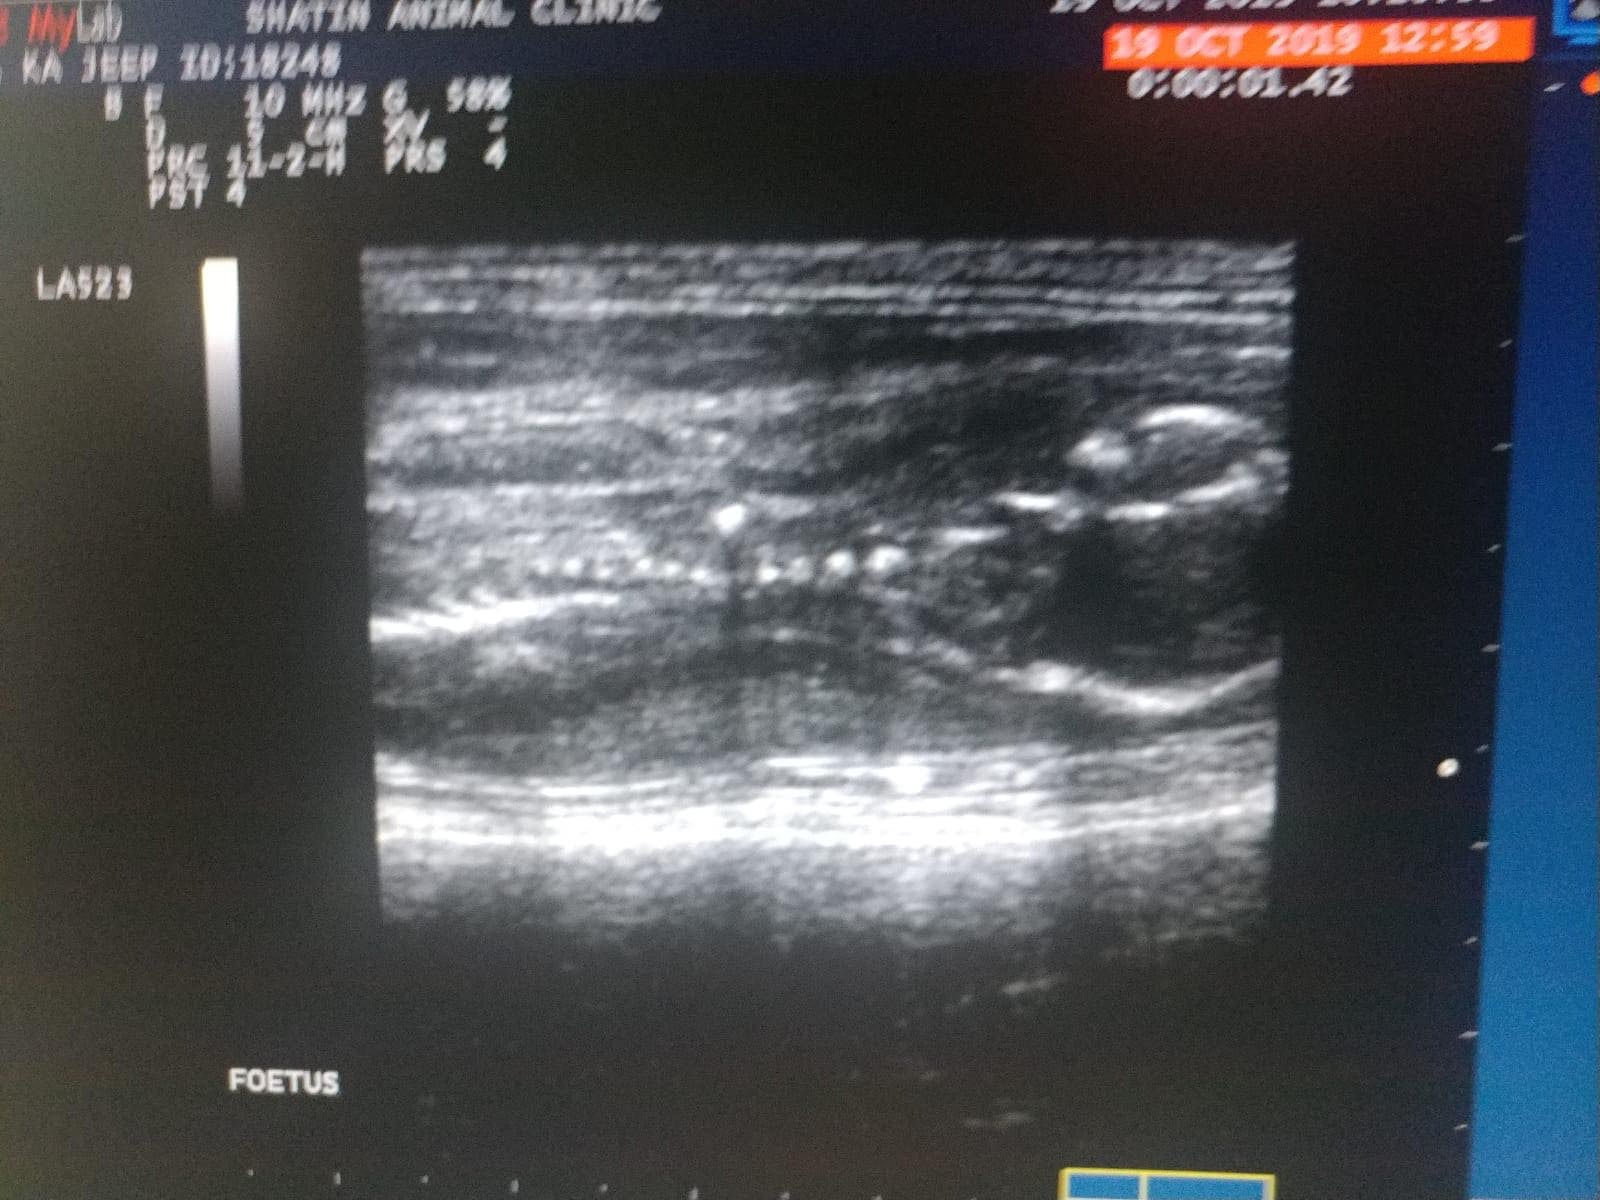

抵達診所後,原本已經鎮定下來的貓咪,突然反常地抓緊籠邊,不願步出貓寵,Kent細看發現籠裏有一個初成型的胚胎。他估計,貓咪子宮被車輛撞擊導致嚴重充血發生流產,醫生隨後為牠照超聲波,發現貓咪肚內還有三隻小貓,每隻只有「手指公咁大」,可惜已經全無生命跡象。貓咪的行為令在場各人感到心酸,決定為牠取名「媽寶」。